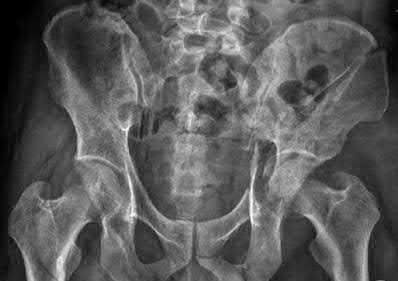

Question 11

A poly-trauma patient presents hemodynamically unstable with an anteroposterior compression (APC-III) pelvic ring injury. A circumferential pelvic binder is requested to reduce pelvic volume and control hemorrhage. To be anatomically effective, the binder must be centered precisely over which of the following landmarks?

Explanation

For optimal mechanical advantage and effective reduction of an 'open book' pelvic fracture (APC type), a pelvic binder must be applied directly over the greater trochanters of the femurs. Applying it higher, such as over the iliac crests, is a common error that fails to adequately close the pelvic ring and can paradoxically open the true pelvis.